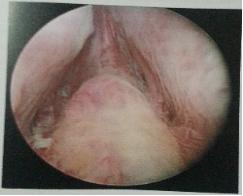

经尿道前列腺电切术:为开展的最早、最为成熟、应用最为广泛的一种微创技术手术。经尿道电切技术始于20世纪30年代,随着经尿道电切设备的不断改进及术者技术的进步和经验的积累,经尿道前列腺电切术(TURP)逐渐在泌尿外科领域广泛应用,目前已经成为良性前列腺增生(BPH)手术治疗的金标准。TURP由于对患者手术创伤小、术后病人恢复快,已被广泛应用于临床,成为治疗良性前列腺增生(BPH)的首选术式。

1)确定标志点:远端标志点-精阜,近端标志点-膀胱颈

2)切除前列腺腺体的主体部分,一般切至前列腺包膜。

3)前列腺尖部切除,此部分切除时须格外注意,避免损伤尿道外括约肌

4)结束电切,将切除组织冲出,再次止血,留置F18-22三腔尿管。